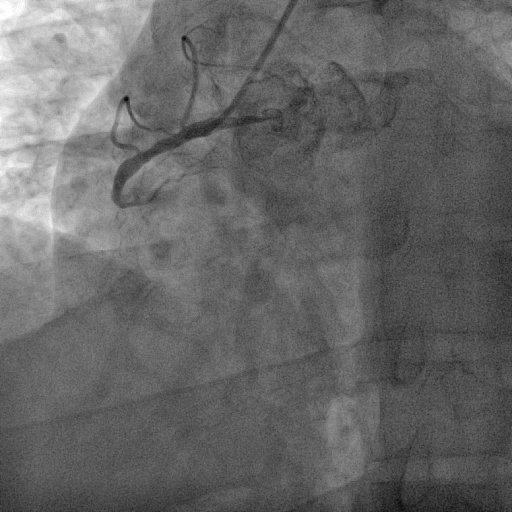

Coronary angiography was performed via right radial access with terumo radial TIG 5Fr catheter . Coronary artery angiogram revealed right dominance coronary artery system with RCA mid 100% with retrograde from LAD and LCx proximal 70%, distal 80% and LAD proximal 99% .

SHAHIDUL ISLAM_(S7_F1-50).avi

SHAHIDUL ISLAM_(S2_F1-57).avi

SHAHIDUL ISLAM_(S6_F1-102).avi